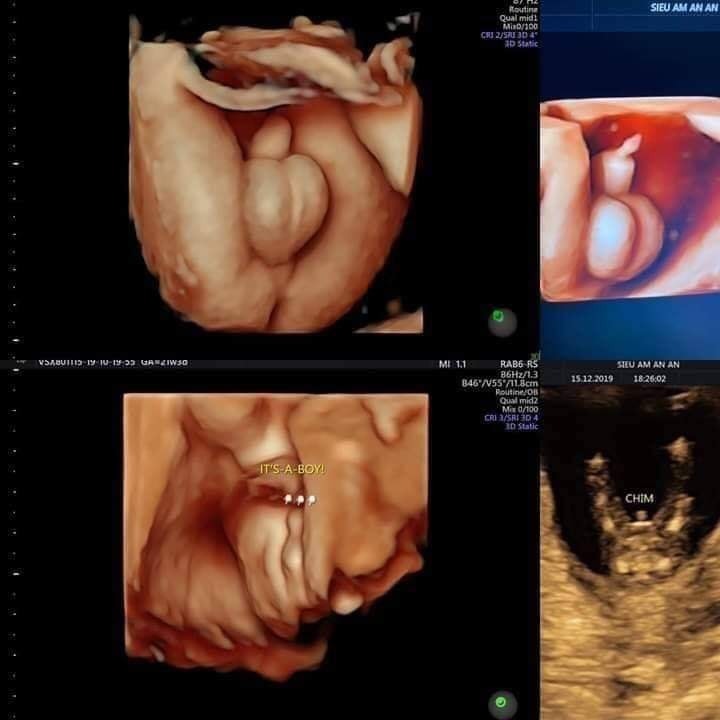

3. Tuần 12: Siêu âm 5D đo độ mờ da gáy (biết đc các dị tật bẩm sinh) và làm doupletest sàng lọc dị tật

4. Tuần 22: siêu âm 5d, hình thái học kiểm tra dị tật tim bẩm sinh ( mốc này rất quan trọng ).Tiêm uốn ván mũi 1 từ 22-26 tuần , mũi 2 cách mũi 1 - 1 tháng.

7. Tuần 32: xem ngôi thai rau ối, sau đó 2 tuần kiểm tra 1 lần